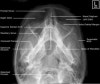

- Adult Facial Bones - Occipitomental(Waters) View